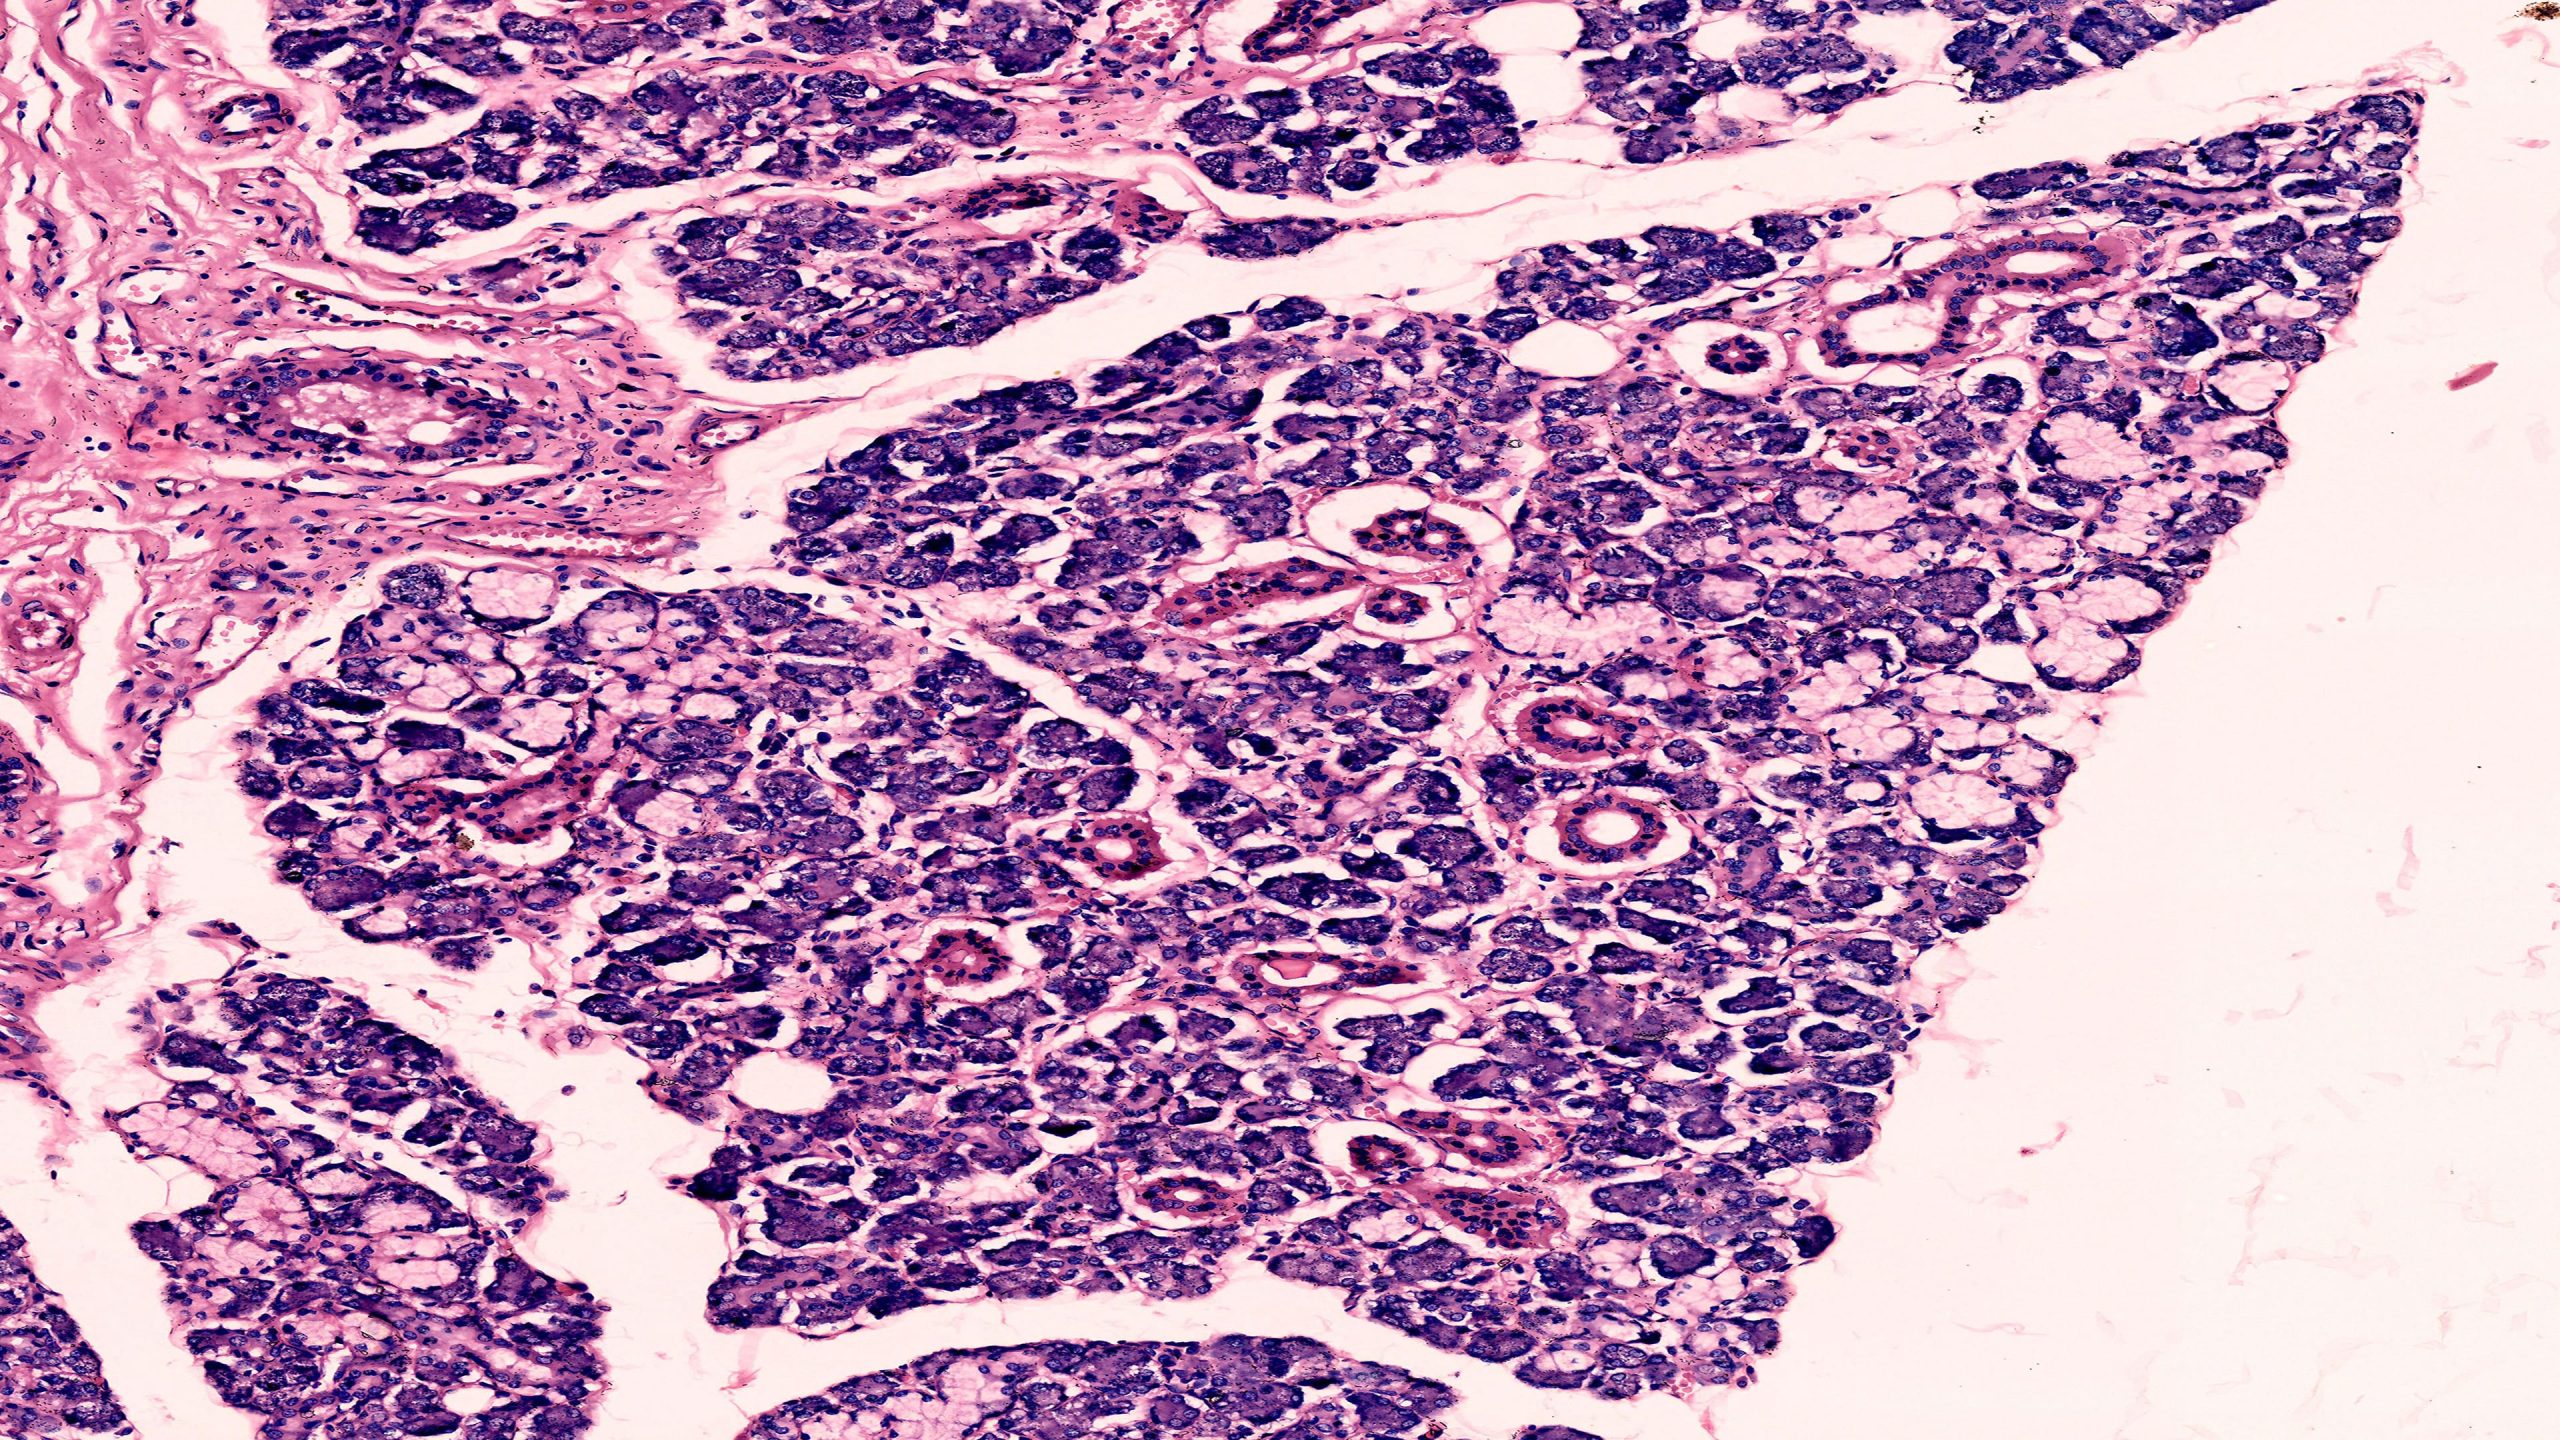

Mixed Salivary Gland 40X